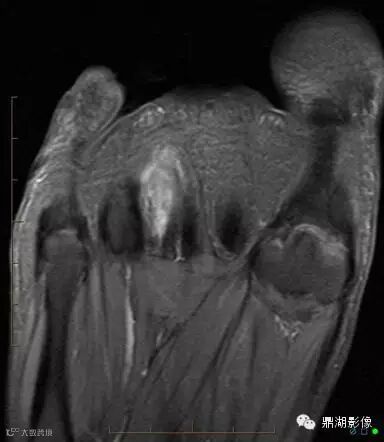

3莫顿神经瘤

高跟鞋与狭窄的鞋尖部分会导致第三和第四个脚趾间的神经周围组织异常增厚,形成莫顿神经瘤。莫顿神经瘤可引起足底尖锐、灼热样疼痛。足趾也可能会出现刺痛、灼热痛,或是麻木的感觉。